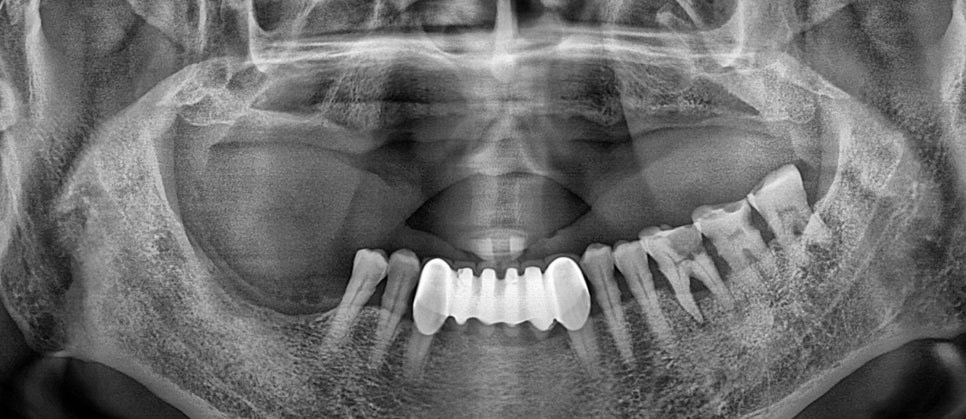

장기간 틀니 사용으로 인해 상악에 잇몸뼈들이 다 녹아내려 없는 모습입니다.

상악에는 전체 임플란트 치료를 하기 위해서 뼈이식을 함께 진행하였습니다.

뼈가 부족하면 임플란트가 제대로 지지를 못하고 추후에 문제가 발생이 됩니다.

튼튼한 잇몸뼈가 받쳐져야 치아의 뿌리를 대신하는 픽스쳐가 제대로 식립이 되고 이후에 보철이 올라갈수 있게 됩니다.

상악의 치아에 임플란트 전체가 보철 올라갈때 까지 총 6개월 정도 소요 되었습니다.